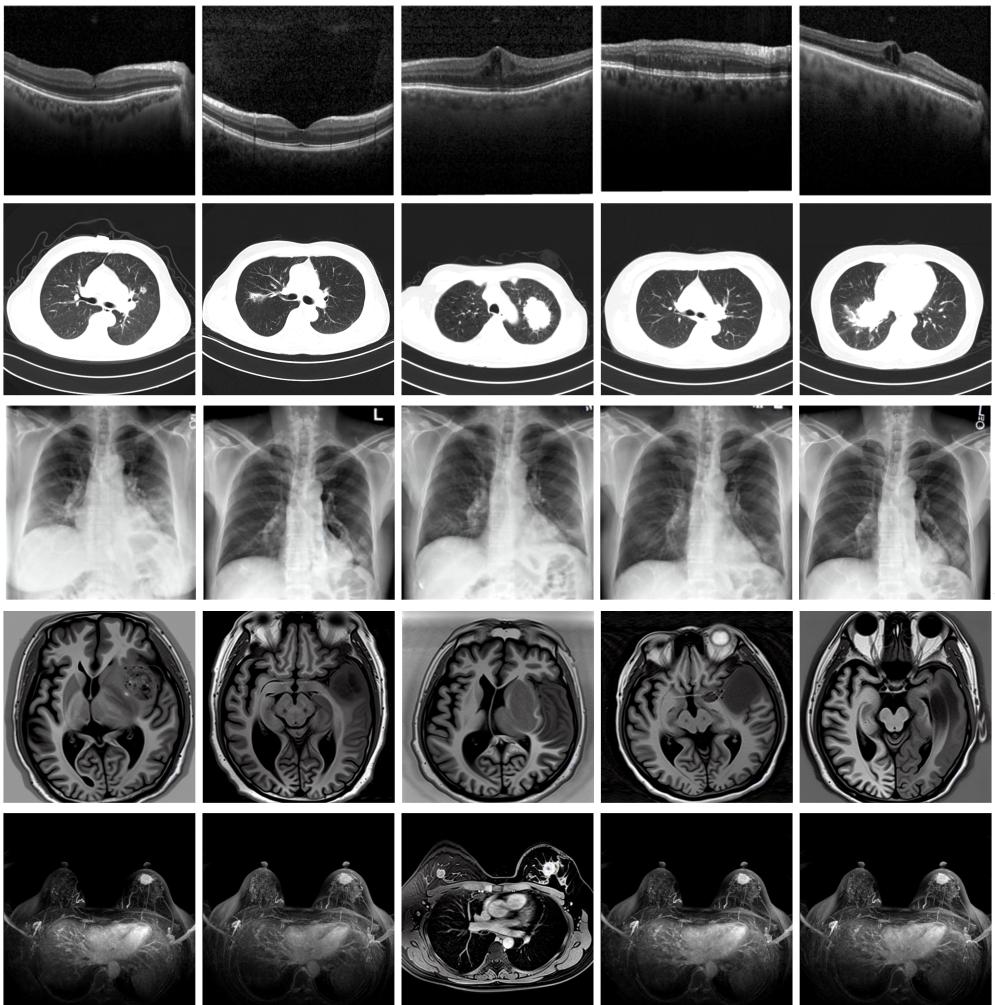

圖為由MINIM生成的高質(zhì)量醫(yī)學(xué)合成圖像(受訪者供圖)

“目前公開的醫(yī)學(xué)影像數(shù)據(jù)非常有限,我們建立的生成式模型有望解決訓(xùn)練數(shù)據(jù)不夠的問題?!北本┐髮W(xué)未來技術(shù)學(xué)院助理研究員王勁卓說,研究團(tuán)隊利用多種器官在CT、X光、磁共振等不同成像方式下的高質(zhì)量影像文本配對數(shù)據(jù)進(jìn)行訓(xùn)練,最終生成海量的醫(yī)學(xué)合成影像,其在圖像特征、細(xì)節(jié)呈現(xiàn)等多方面都與真實醫(yī)學(xué)圖像高度一致。

實驗結(jié)果顯示,MINIM生成的合成數(shù)據(jù)在醫(yī)生主觀評測指標(biāo)和多項客觀檢驗標(biāo)準(zhǔn)方面達(dá)國際領(lǐng)先水平,在臨床應(yīng)用中具有重要參考價值。在真實數(shù)據(jù)基礎(chǔ)上,使用20倍合成數(shù)據(jù)在眼科、胸科、腦科和乳腺科的多個醫(yī)學(xué)任務(wù)準(zhǔn)確率平均可提升12%至17%。